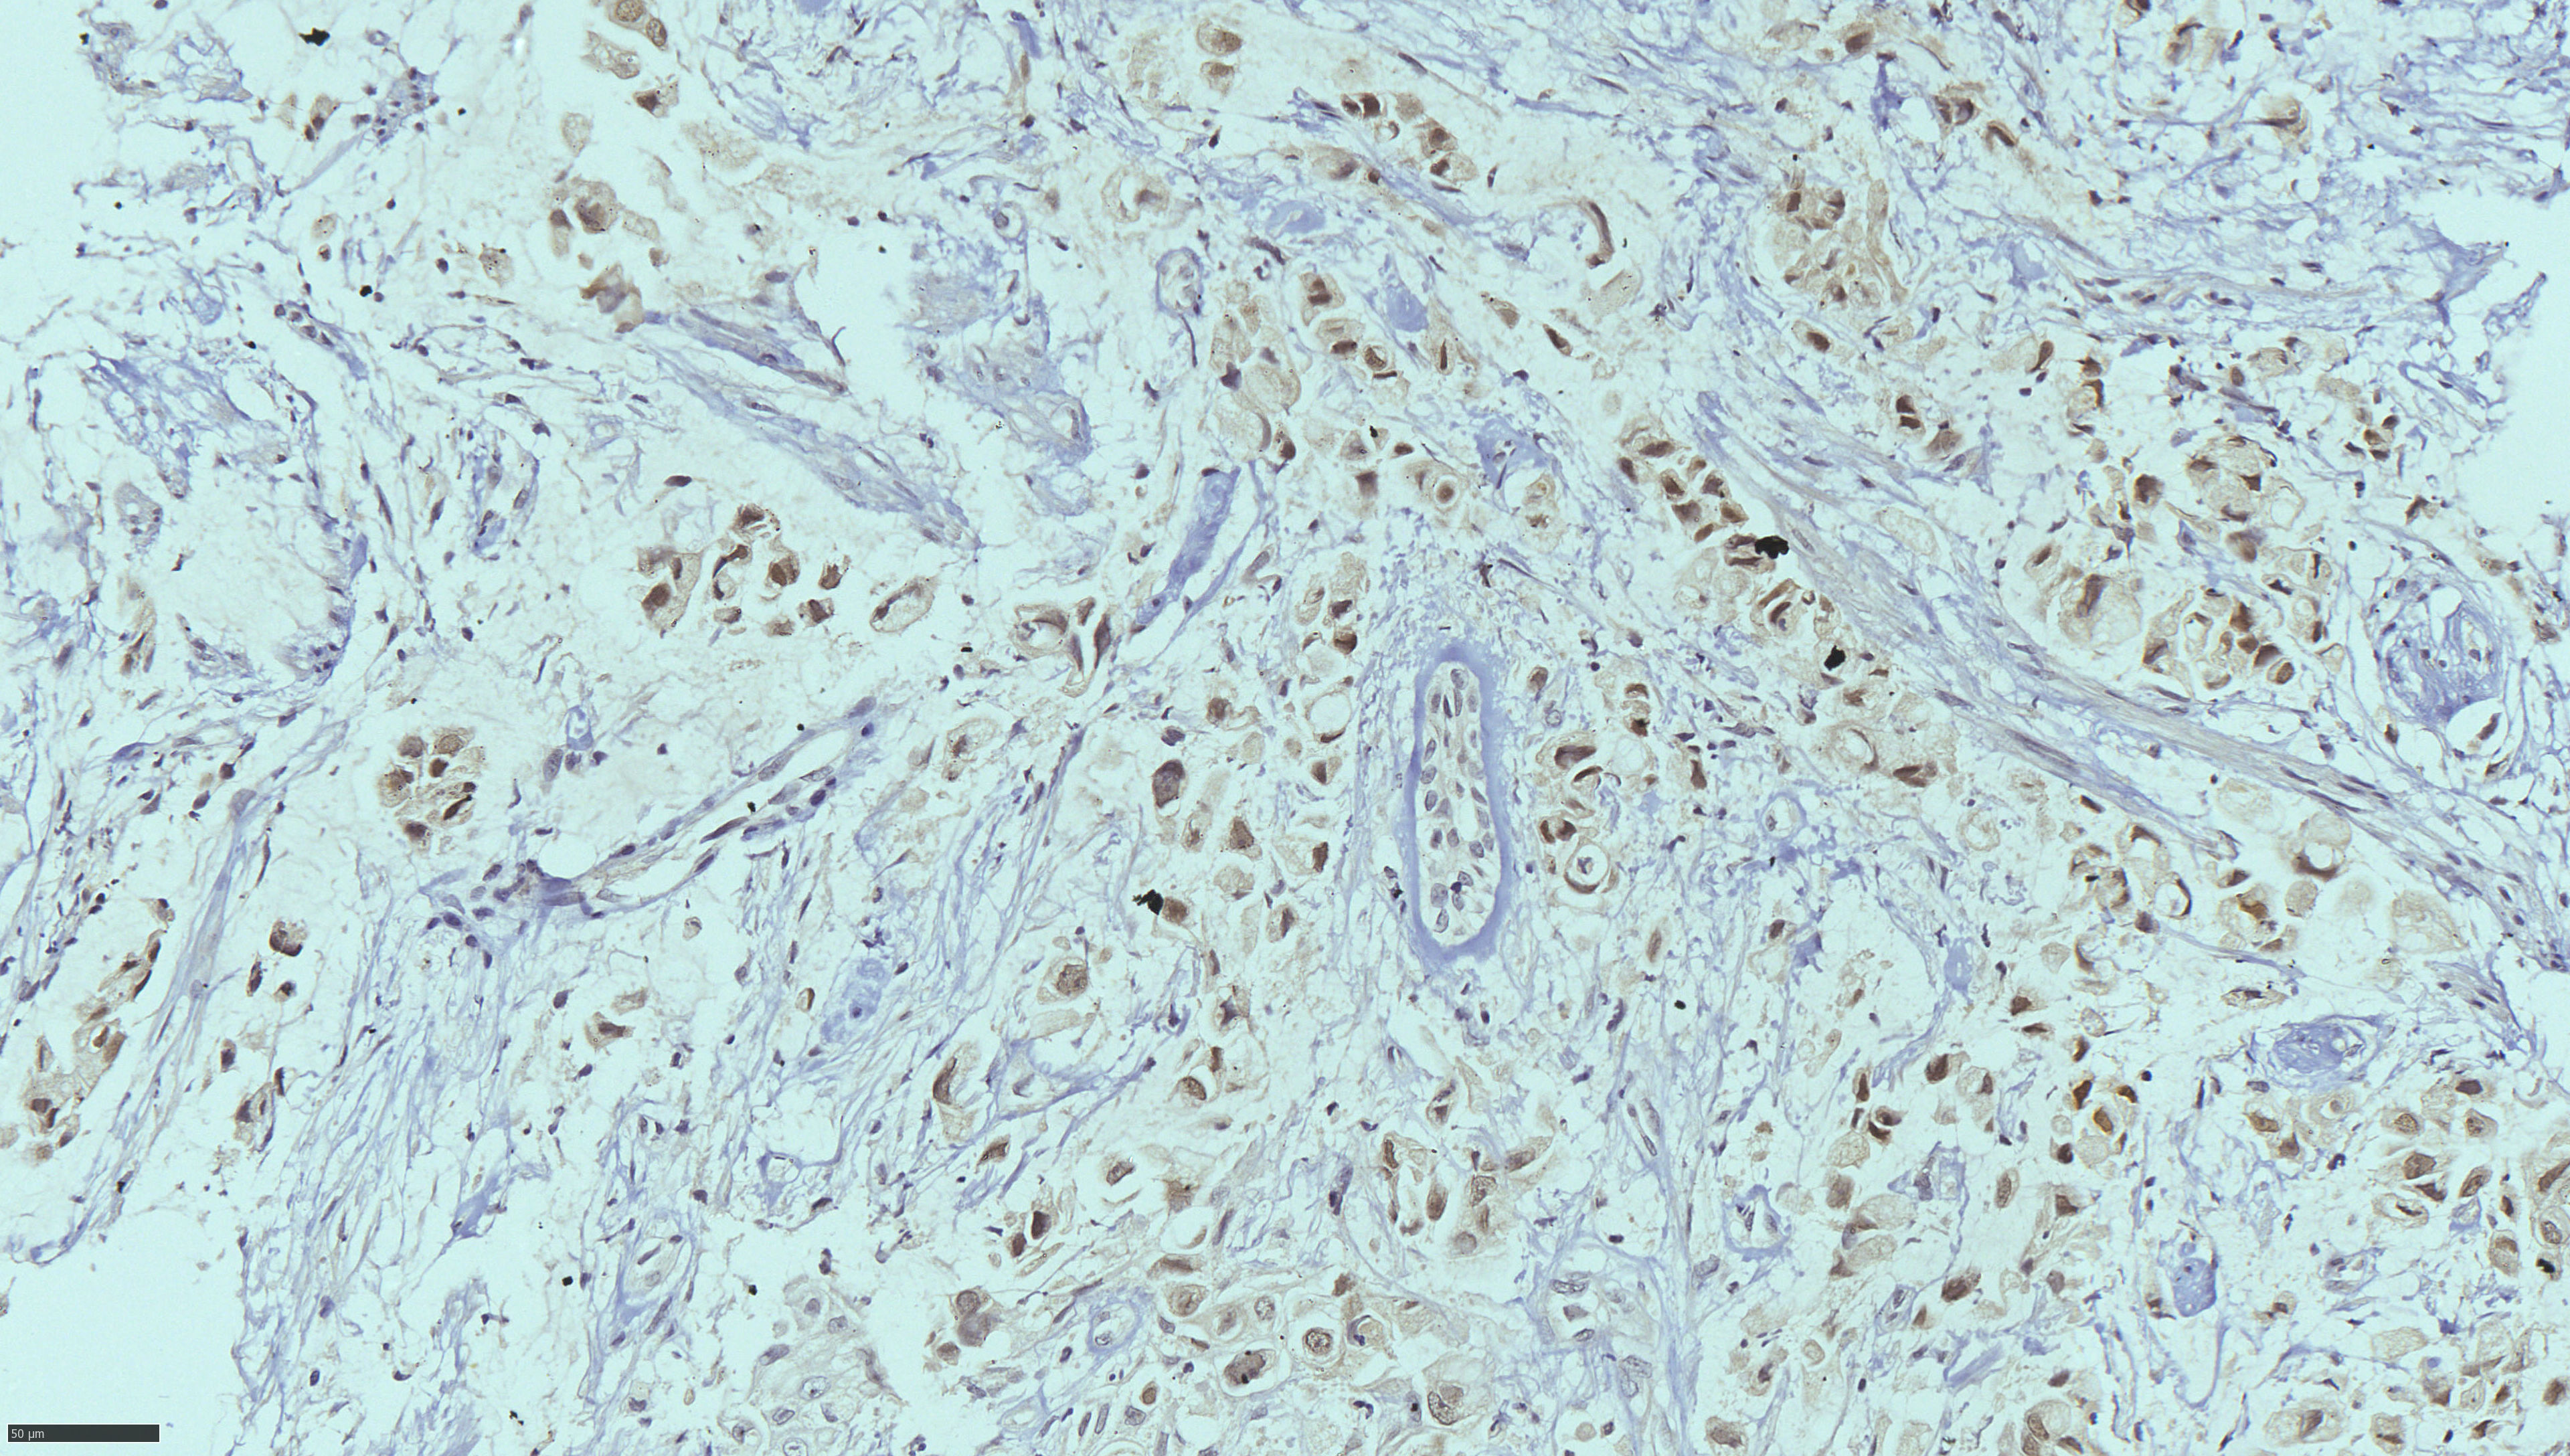

Image Gallery & Slides

Pathology images, lab photos and recent slides. Replace these with higher resolution images from your collection when ready.

To add more images: put your files into the images/ folder and update the <img src="images/yourfile.jpg"> paths below.